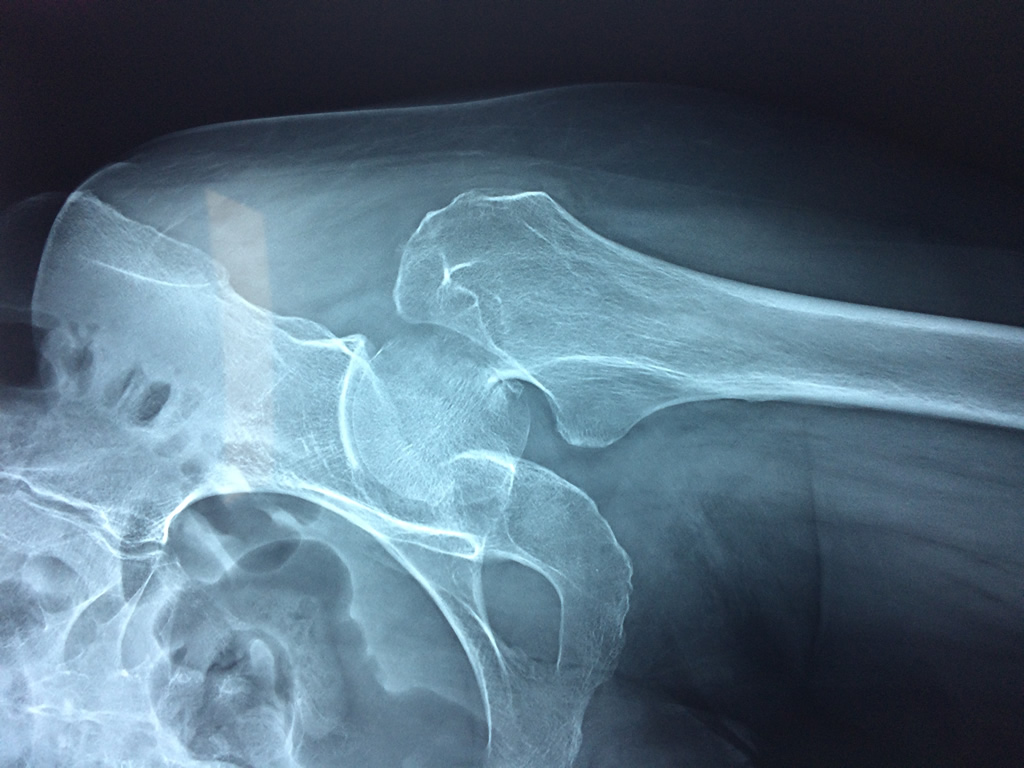

Clavícula

La cirugía de fractura de cadera se realiza para reparar una ruptura en la parte superior del hueso del muslo. Este hueso se denomina fémur.